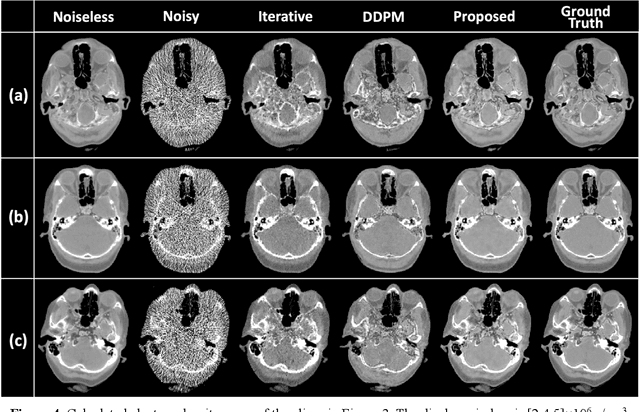

Abstract:Background: Dual-energy CT (DECT) and material decomposition play vital roles in quantitative medical imaging. However, the decomposition process may suffer from significant noise amplification, leading to severely degraded image signal-to-noise ratios (SNRs). While existing iterative algorithms perform noise suppression using different image priors, these heuristic image priors cannot accurately represent the features of the target image manifold. Although deep learning-based decomposition methods have been reported, these methods are in the supervised-learning framework requiring paired data for training, which is not readily available in clinical settings. Purpose: This work aims to develop an unsupervised-learning framework with data-measurement consistency for image-domain material decomposition in DECT.